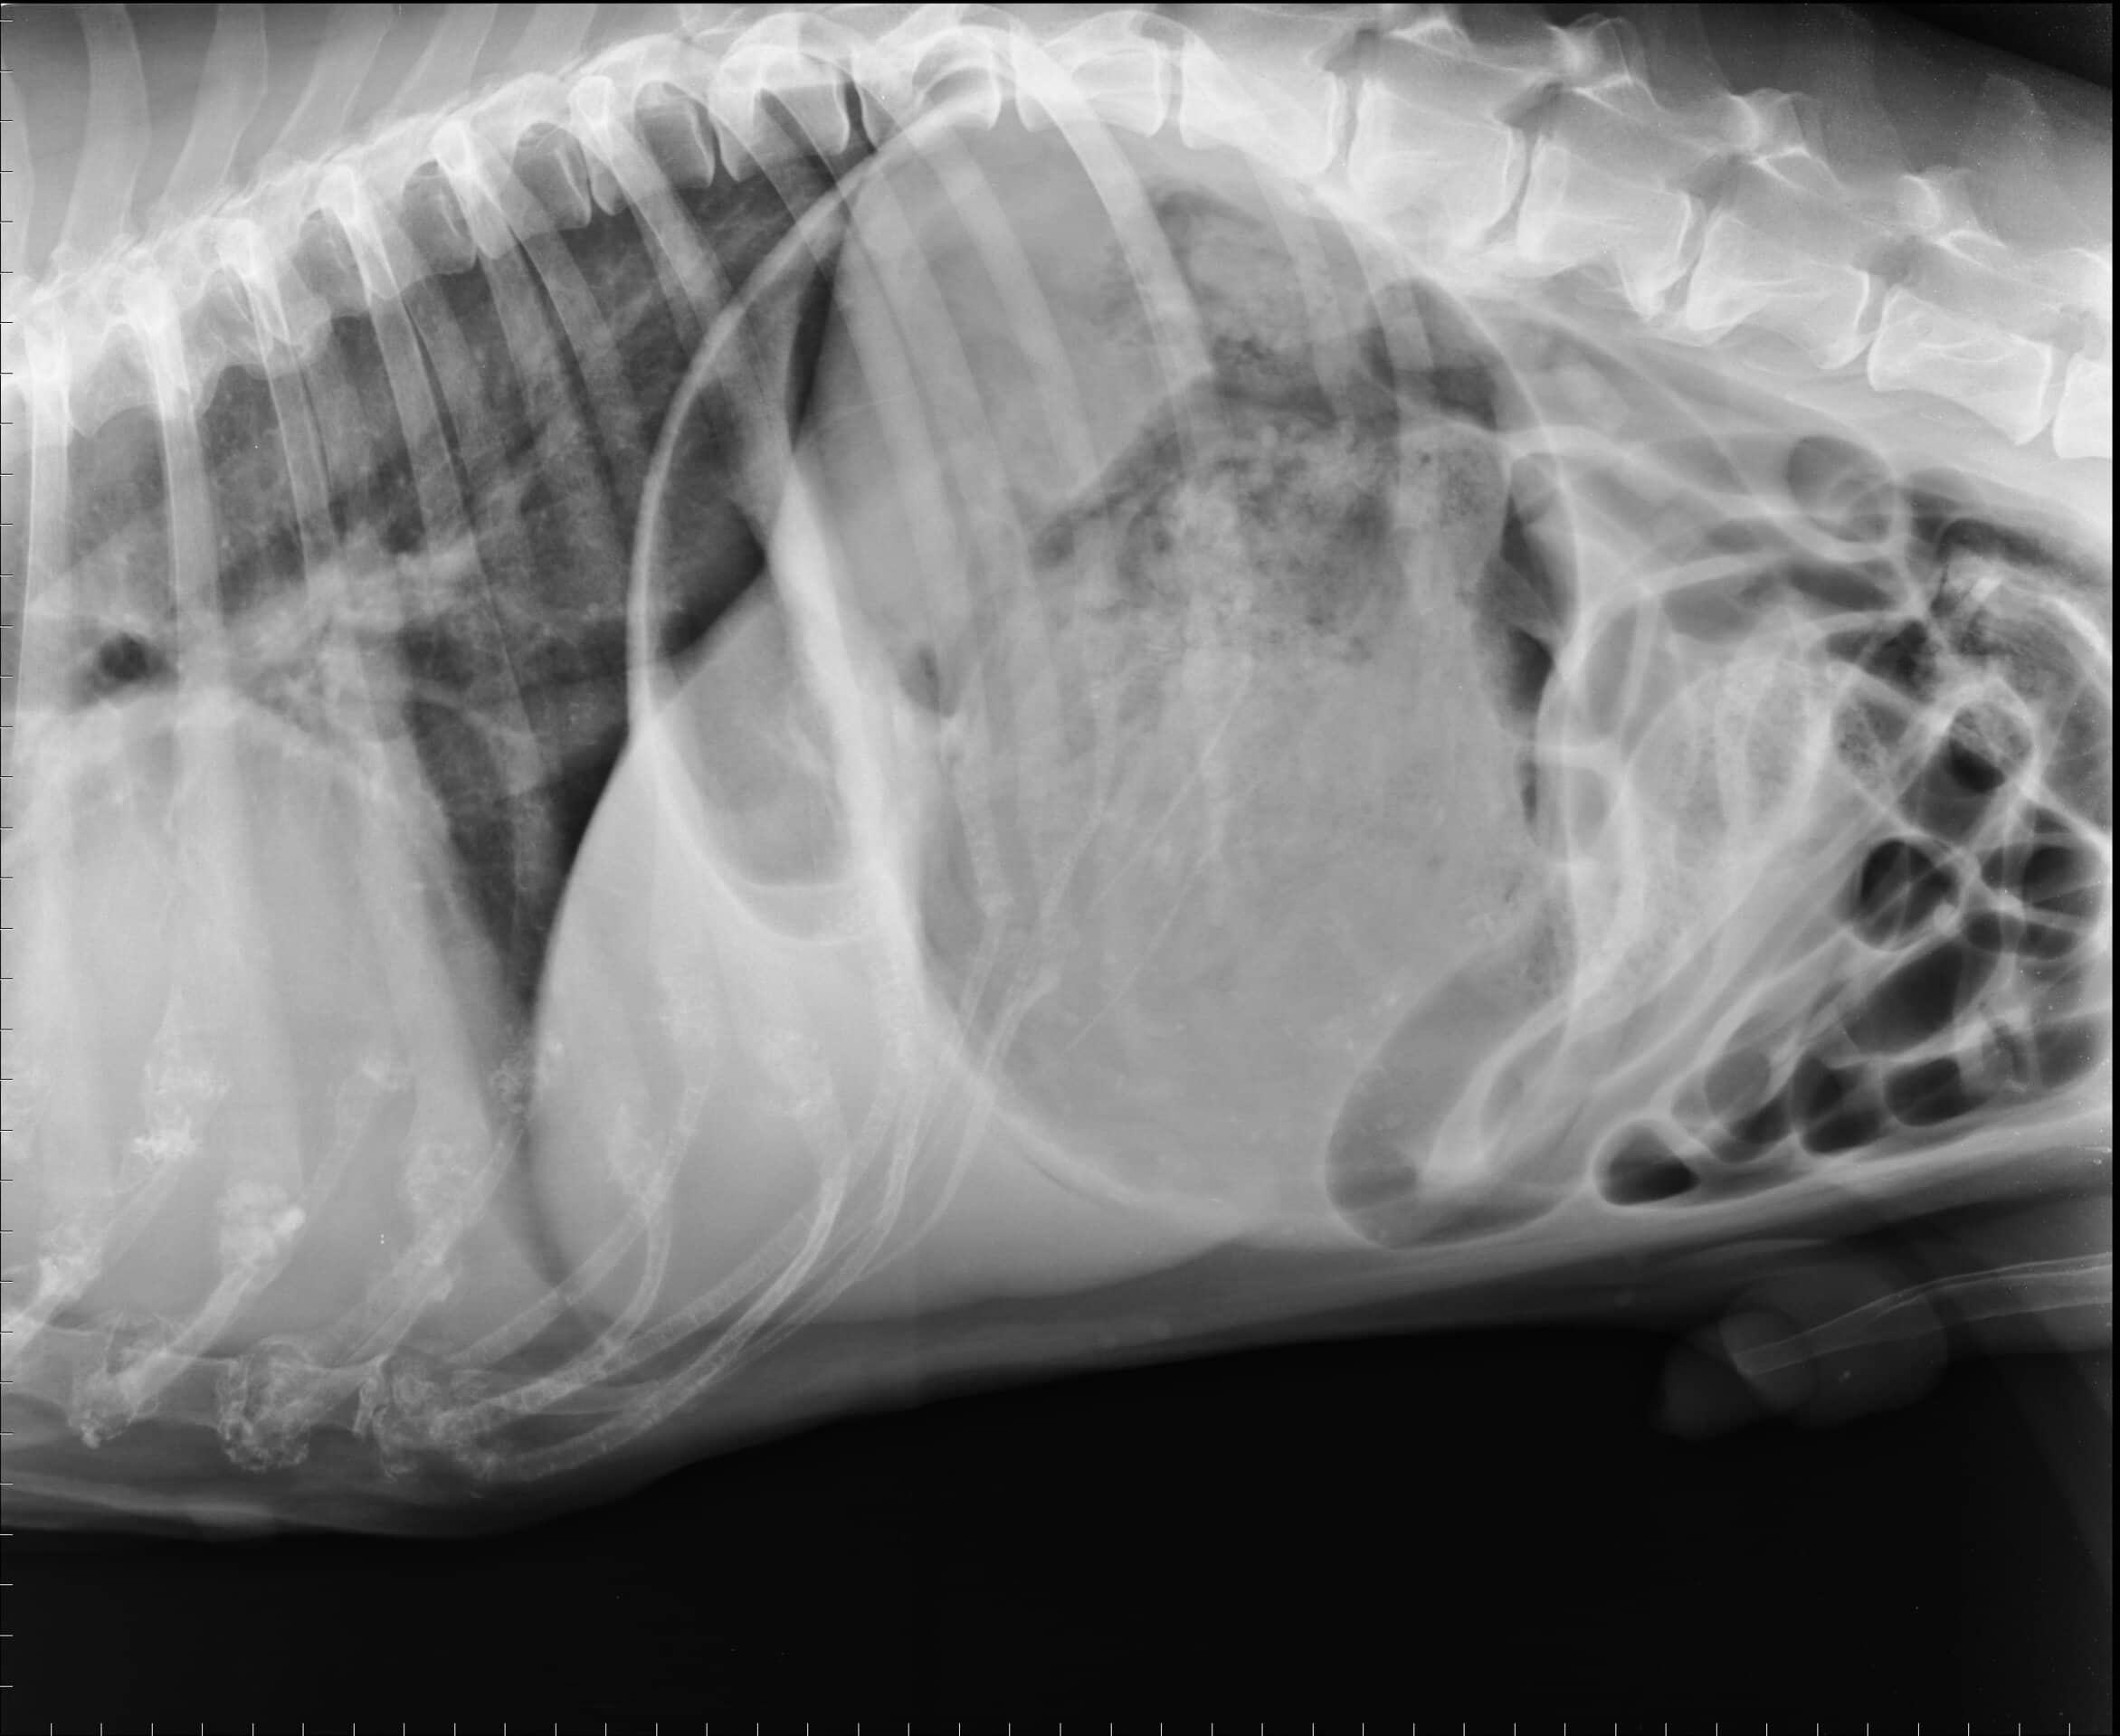

Il tuo cane mangia, come sempre, magari avidamente come sempre. E tutto va bene. Poi improvvisamente ti accorgi che si comporta in modo strano: si accascia, respira con difficoltà, cerca di vomitare ma non ci riesce, il suo addome si gonfia! Devi correre dal veterinario! Lo stomaco infatti ha fatto un giro di 360° su se stesso chiudendo il passaggio bocca-esofago e quello successivo verso l’intestino.

Non può svuotarsi ma, quello che è peggio, continua a gonfiarsi, i vasi sanguigni che irrorano lo stomaco si stirano, viene coinvolta anche la milza perché legata allo stomaco. Abbiamo aritmie cardiache, gravi disturbi elettrolitici… anche solo pochi minuti possono fare la differenza!